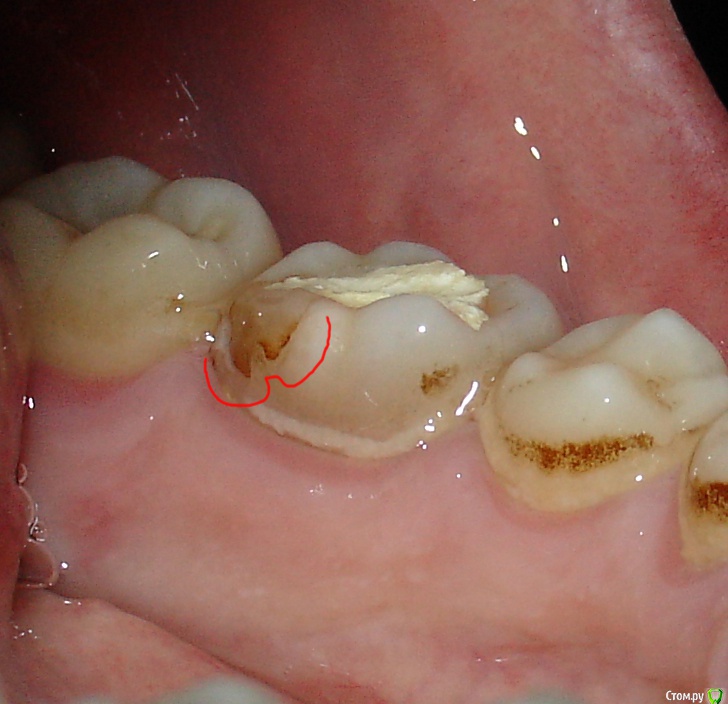

Madbus Опубликовано 25 июля, 2019 Автор Поделиться Опубликовано 25 июля, 2019 Подскажите пожалуйста - начал перелечивать 36 зуб, сделали повторную чистку каналов, поставили лекарство и временную пломбу. То, что зуб болит я так понимаю допустимо, но чувствую какой-то привкус во рту, решил осмотреть зуб и как мне кажется есть трещина и возможно ли, что через неё и выходит лекарство? Ссылка на комментарий

DmitrySH Опубликовано 25 июля, 2019 Поделиться Опубликовано 25 июля, 2019 Сложно по фото сказать насколько герметична пломба в том месте. Лучше сообщить своему врачу. И надо налаживать гигиену полости рта, очень много мягкого налета 2 Ссылка на комментарий